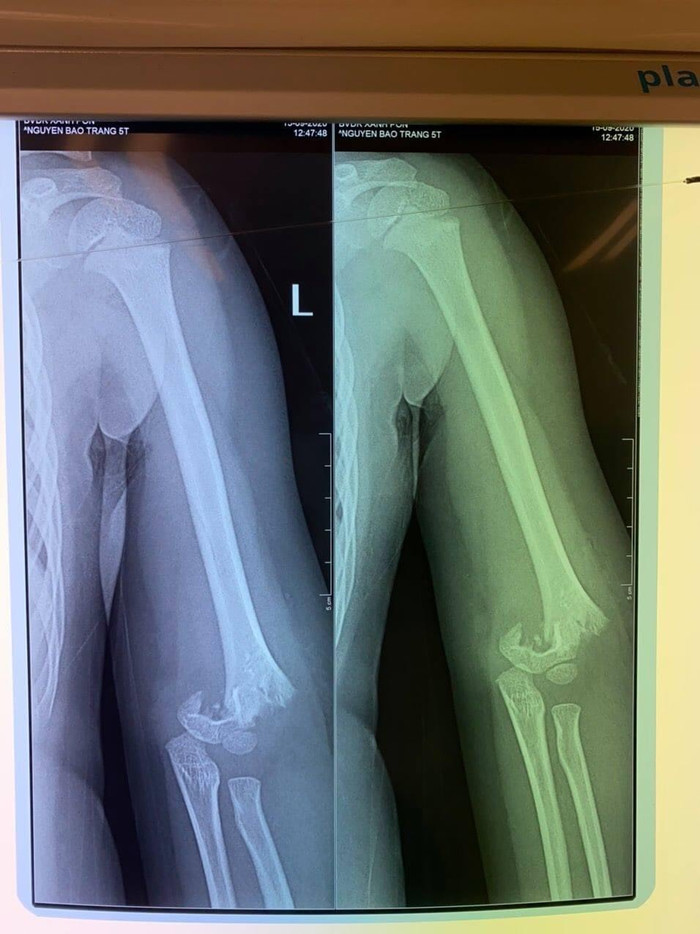

Tại bệnh viện, khi cô giáo thông báo cho mẹ cháu bé vào làm thủ tục để nhập viện, khi đó chị H. vô cùng bất ngờ khi biết con bị mổ cấp cứu, có nguy cơ bị liệt, đau đớn hơn khi xem phim chụp thấy hình ảnh xương ở khuỷu tay của con đã bị gãy lìa.